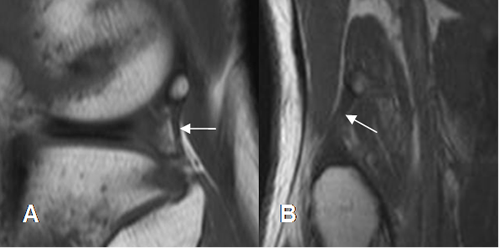

Fig 28. Ligamento arcuato normal.

A: RM coronal en T1 y B: RM coronal en STIR. Ligamento normal, por engrosamiento posterior de la cápsula.